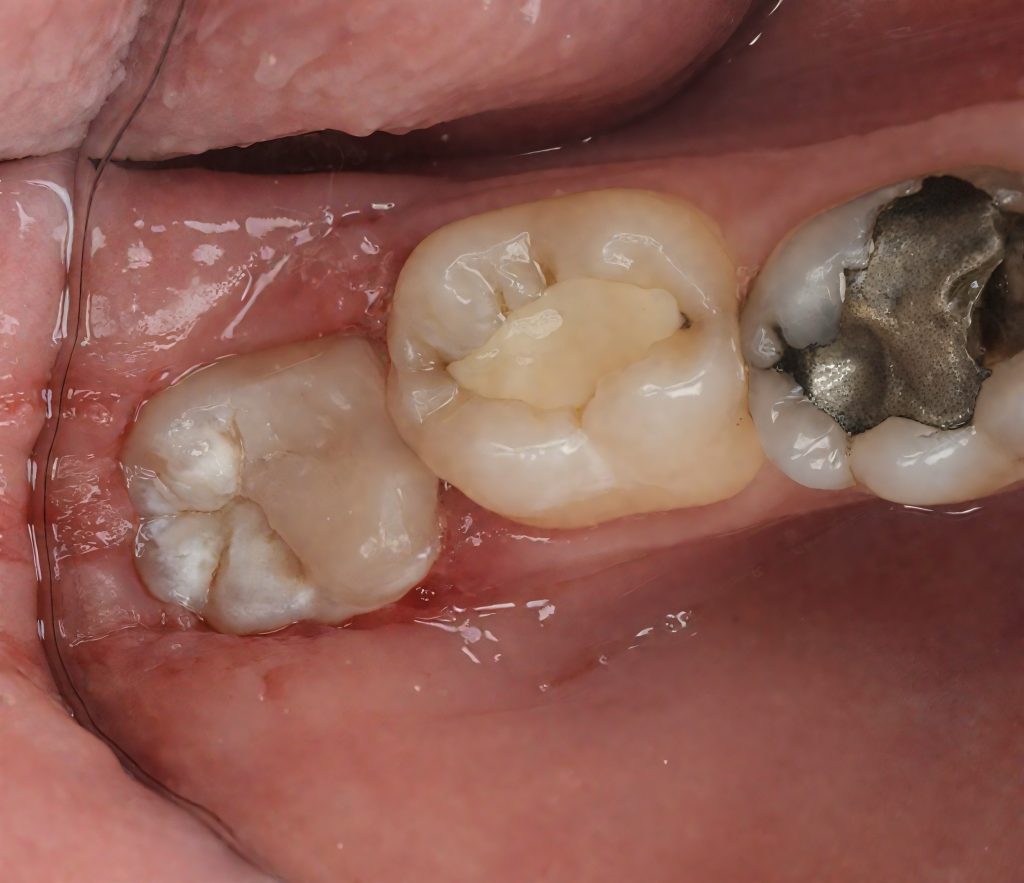

Caries excavation performed conservatively, preserving enamel ridges. Distal sub-gingival margin elevated using the Matrix-within-Matrix DME technique with a sectional matrix system and Teflon-assisted adaptation. This enabled proper contact form and a cleansable margin (Fig 3).

- Fig 3: Deep marginal elevation with Matrix-within-Matrix technique.